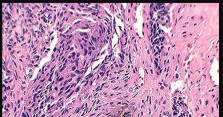

Mutations in the isocitrate dehydrogenase genes, IDH1 and IDH2, are found in up to 50-60% of central conventional chondrosarcomas and enchondromas. EXT1 and EXT2 mutations are characteristic of multiple hereditary exostoses (osteochondromas). GNAS mutations are seen in fibrous dysplasia. TP53 and RB1 mutations are hallmark aberrations in osteosarcoma.